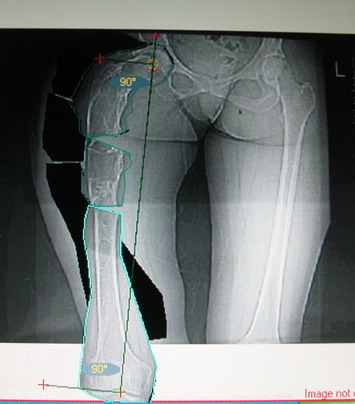

Моё мнение, что двойная остеотомия бедра с аппаратом Илизарова + Гексаподный механизм, или Тэйлора, В данной ситуации является методом выбора. Я очень извеняюсь за качество прилагаемых снимков, в которых я постарался отразить разницу междe одной и двумя остеотомиями бедра.